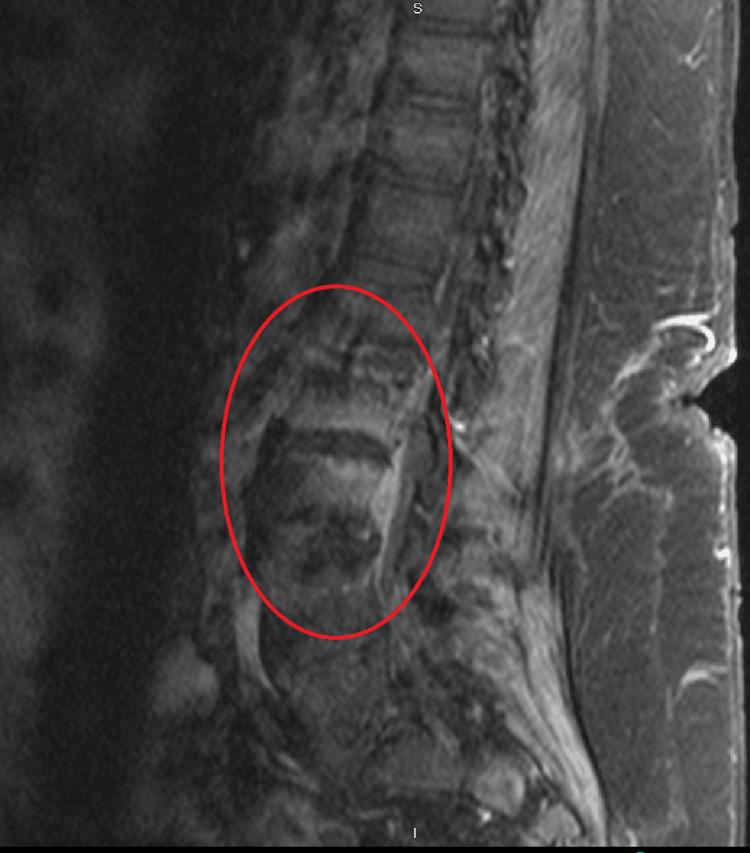

Telavancin is a fairly novel antibiotic derived from vancomycin developed to combat the constant evolutionary war against bacteria. It has achieved high clinical success in its role in treating Gram-positive organisms, although like in the case of any other antibiotics, failure can arise. The purpose of this article is to describe a case in which telavancin clinically failed in treating persistent methicillin-resistant (MRSA) bacteremia in a patient while describing the cause that led to telavancin failure.

特拉万星是一种相当新颖的抗生素,由万古霉素衍生而来,用于对抗与细菌持续不断的进化之战。它在治疗革兰氏阳性菌方面取得了很高的临床成功率,尽管与任何其他抗生素一样,也可能出现治疗失败的情况。本文旨在描述一例特拉万星在临床上治疗一名患者的持续性耐甲氧西林金黄色葡萄球菌(MRSA)菌血症失败的病例,并阐述导致特拉万星治疗失败的原因。